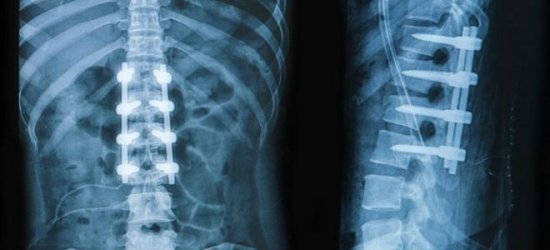

Рентген позвоночника

Неотъемлемая составляющая диагностики болей в спине – инструментальные исследования

После обращения к травматологу потребуются лабораторные и аппаратные исследования, включающие в себя: анализ мочи и крови, рентгенографию, МРТ, электрокардиограмму . При лечении применяются как классические методы (фиксация и восстановление повреждённого позвонка), так и хирургические.

Почему болит низ спины, может установить только врач. Ни в коем случае не следует заниматься самодиагностикой и самолечением. Диагноз ставится на основании жалоб больного, клинических проявлений, анамнестических данных, результатов инструментальных методов исследования. Пациенту назначают рентгенографию, миелографию, МРТ, КТ и другие виды обследований.

Компьютерная томография является эффективным и высокоинформативным способом выявления различных структурных изменений в позвоночнике, вызванных травматизацией, инфекционным процессом, опухолевыми образованиями, остеопорозом и другими заболеваниями. В основе миелографии лежит применение контрастирующего вещества. Метод применяют при подозрении на стеноз позвоночного канала, грыжевых образованиях, опухолях и других патологических процессах в позвоночнике.